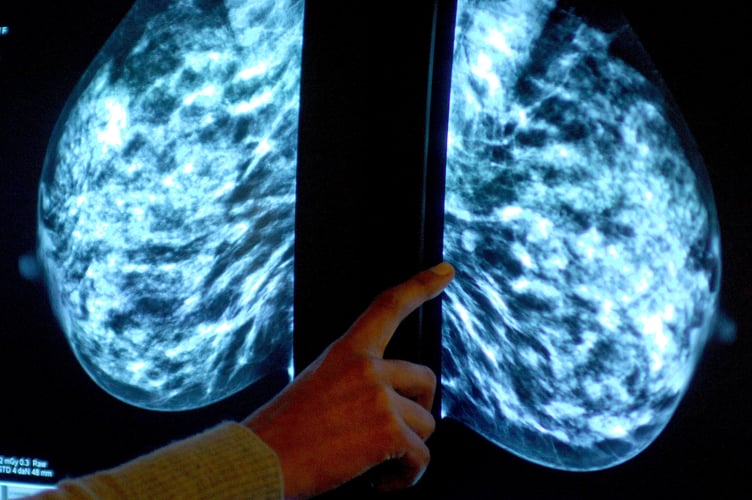

Anyone registered with a GP as female will be invited for NHS breast screening every three years between the ages of 50 and 71.

Dr Claire Knight, senior health information manager at Cancer Research UK, said: "Breast screening is an important tool for spotting the early signs of breast cancer at a stage when treatment is more likely to be successful.

"The current evidence suggests that breast screening reduces the number of deaths from breast cancer by about 1,300 a year in the UK."